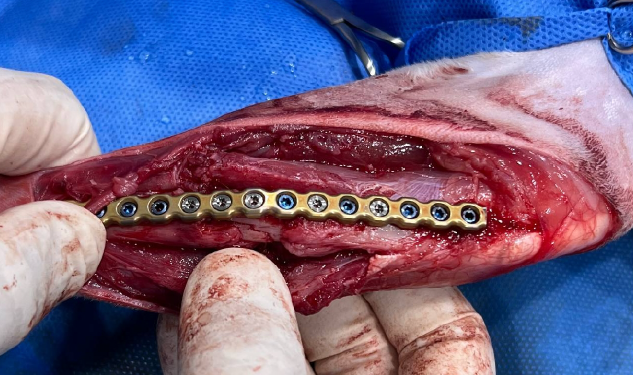

플레이트로 고정하는 수술이었는데 플레이트의 수명이 20년 정도라 추후에 이상만 없다면 반영구적으로 고정하게 된다고 합니다.

골절 수술은 최대한 빨리 진행하는 것이 결과가 좋다고 해서 2차병원에 예약하자마자 바로 수술을 진행하고 4일간 입원하였습니다. 골절 구조의 어려움 때문에 발견 후 3-4일 정도 망설였는데 병원에서 골절은 골든 타임이 중요하다고 하셔서 다람이한테 미안해지는 순간이었습니다. 발견하자마자 수술을 했더라면 훨씬 뼈도 빨리 붙고 덜 아팠을 텐데. 다리 털을 밀고 보니 멍이 들어 있었습니다.(사진 참고)

다행이 수술은 잘 진행되었고 추후에 뼈가 붙는 과정이 관리가 매우 중요하다고 해서 임시 보호에 신경을 많이 쓰게 되었습니다. 넥카라를 하며 다른 고양이들과 격리하여 베란다에서 지내게 되었고 다리에 위험이 되는 공간은 치워주었습니다.